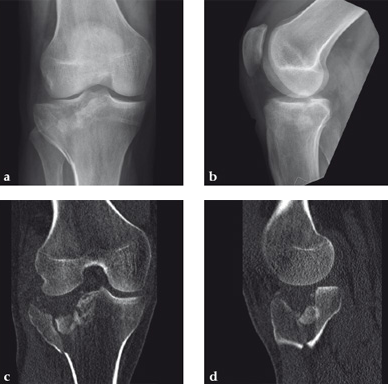

Case 2: A 38-year-old man sustained a lateral tibia plateau fracture (Müller AO Classification 41-B.3/Schatzker type II).

(Case provided by Michiel Verhofstad, Tilburg, The Netherlands)

After opening the lateral wedge, the osteochondral fragment was reduced and maintained with two K-wires. A gap beneath this fragment was left. Subsequently, a 3.2 mm hole was drilled in the lateral wedge using an inside-out technique. Then the lateral fragment was reduced. A 3-hole buttress plate, followed by two subchondral compression screws were used for final fracture fixation. Finally, Norian drillable was injected in the gap through the predrilled hole. Weight bearing was started after 6 weeks. At 6 months the fracture had healed anatomically and the patient was complaint-free.